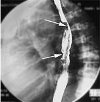

Рентген пищевода. Это инструментальный метод диагностики, позволяющий визуализировать пищевод с помощью рентгеновских лучей. Во время исследования можно определить положение этого органа, структуру стенок и сфинктеров, размер просвета, а также сделать выводы о характеристиках его моторика. Рентгенограмма пищевода выявляет такие патологические изменения, как воспаление, дивертикулы, новообразования, грыжа пищевода, открытие диафрагмы, разрыв пищевода, аномалии развития, язвы, кровотечение и перфорация стенки. Это исследование обычно проводится как самостоятельная процедура. Специфической рентгенологической подготовки пищевода в большинстве случаев не требуется, некоторым пациентам сначала рекомендуется соблюдать голод.

Результаты рентгенографии пищевода могут выявить следующие заболевания: эзофагит, гастроэзофагеальная рефлюксная болезнь, дивертикул, аномалии развития, дистопия, стеноз и разрыв пищевода, новообразования, грыжа пищевода, открытие диафрагмы, язвенная болезнь или кровотечение, осложненное перфузией. Наличие на рентгенограмме эзофагита, язвенной болезни, дивертикула и новообразований пищевода свидетельствует о нарушении нормальной структуры стенки.

При разрыве на картине пищевода происходит «разрыв» органа и выделение сульфата бария в брюшную полость или средостение, во время перфорации - дефект сквозной стенки, который также сопровождается выделением контраста за пределами просвет. Стеноз и аномалии развития характеризуются сужением полости пищевода или его полным перекрытием с проксимальным расширением стенок. Грыжа пищеводного отверстия диафрагмы при рентгенографии пищевода проявляется расширением кардиального отдела, выходом в грудную полость части или всего желудка. Структурные нарушения сердечного сфинктера могут указывать на ГЭРБ.